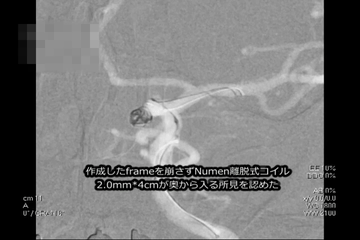

NUMEN Case 18

NUMEN Case 20